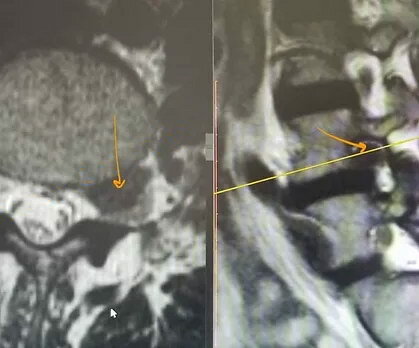

Наиболее информативным методом диагностики является магнитно-резонансная томография (мощность магнита не менее 1,5 Тесла) пояснично-крестцового отдела позвоночника тонкими срезами в трех плоскостях.

На МРТ показана фораминальная грыжа. Видно, что она находится сбоку от позвоночного канала - в межпозвонковом отверстии, где проходит спинномозговой корешок (серое образование ниже черной грыжи, если смотреть прямо на МРТ).